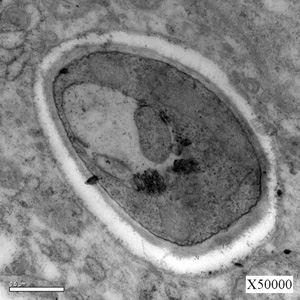

图2、3:肠组织切片电镜下病原体形态。电镜下黑热病利杜体由内外两层表膜包被,每一层为一个单位膜。在内层表膜下有排列整齐的管状纤维,称为膜下微管。虫体前端的表膜向内凹陷,形成一袋状腔,称为鞭毛袋,内有一根很短的鞭毛(即光镜下的根丝体)。基体为中空圆形,动基体为腊肠状。